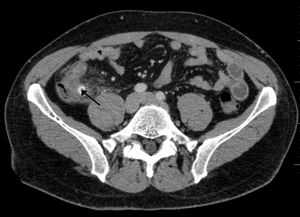

CT 스캔은 급성 충수염을 진단하는데 사용된다.[36] 의사는 환자의 병력과 증상을 평가하고, 신체 검사를 시행하며, 검사실 및 영상 검사를 모두 주문한다. 비전형적인 증상을 보이는 경우에는 초음파나 CT 스캔과 같은 영상 검사가 필요하다.[12] 소아는 방사선 노출 위험 때문에 초음파 검사를 우선적으로 시행하며, 결과가 불확실한 경우에만 CT 스캔을 추가로 시행한다.[54][55][56] 성인 및 청소년의 경우 CT 스캔이 초음파 검사보다 더 정확하며, 민감도 94%, 특이도 95%를 보인다. 반면 초음파 검사는 민감도 86%, 특이도 81%이다.[57]복부 초음파 검사, 특히 도플러 초음파는 특히 소아에게서 충수염 진단에 유용하다. 초음파 검사에서는 오른쪽 장골와에서 액체 저류, 컬러 도플러 사용 시 혈류 증가, 충수의 비압착성 등이 관찰된다. 급성 충수염의 다른 징후로는 충수 주변의 에코성 장간막 지방, 충수 결석의 음향 그림자 등이 있다.[58] 약 5%의 경우, 장골와 초음파 검사에서 이상이 발견되지 않지만, 이는 초기 충수염이거나 지방과 장내 가스로 인해 충수 확인이 어려운 성인에게서 흔하게 나타난다. 숙련된 검사자는 초음파 영상을 통해 충수염과 유사한 증상을 보이는 림프절 염증, 난소 또는 나팔관 문제 등을 구별할 수 있다.[60] 초음파 검사는 방사선과나 응급 의학 전문의가 시행할 수 있다.

컴퓨터 단층 촬영술(CT)은 병력 및 신체 검사에서 진단이 불확실한 경우에 자주 사용된다. 2019년 코크란 리뷰에 따르면 성인 급성 충수염 진단에 대한 CT의 민감도와 특이도는 높다.[62] 그러나 방사선 노출 우려로 인해 임산부와 어린이에게는 CT 사용을 제한하고, 자기 공명 영상(MRI) 사용이 증가하는 추세이다.[63][64]

충수염 진단은 충수 크기가 가장 중요하며, 6mm 이상이면 민감도와 특이도가 모두 95%이다.[65] 그러나 충수가 분변 물질로 채워져 팽창된 경우에는 진단이 어려울 수 있다.[66] 이 경우 초음파 검사가 유용하며, 주변 장에 비해 벽의 조영 증강, 주변 지방 염증 등의 특징으로 진단을 돕는다. 심한 경우 농성 염증, 고름집, 고름이나 장 내용물 누출로 인한 골반 내 액체 층이 관찰될 수 있다. 마른 환자는 지방 부족으로 충수와 주변 염증 관찰이 어려울 수 있다.[66]

CT 검사에서 충수 부종이나 주변 지방 조직 농도 상승이 관찰되며, 조영제 사용 시 민감도와 특이도가 모두 98%로 정확도가 높다. 최신 초음파 검사 장비는 맹장 형태 평가에 유용하지만, 맹장 위치나 장비, 검사자 숙련도에 따라 진단이 어려울 수 있다. 최근 소아 충수염 진단에서 컴퓨터 단층 촬영(CT) 검사는 감소하고 초음파 검사는 증가했지만, 임상 경과에는 변화가 없다는 보고가 있다.[126]